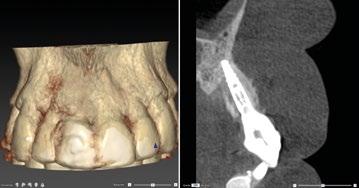

Planificación digital

La planificación comienza con un CBCT para evaluar la densidad ósea del cuerpo cigomático, región pterigoidea y pared lateral de la cavidad nasal. Se realiza incisión crestal o vestibular extendida con colgajo mucoperióstico para exponer el reborde residual. Los implantes

cigomáticos se colocan con angulación hacia el cuerpo del cigoma desde el sector premolar, con perforación bicortical. Es esencial el estudio imagenológico con CBCT y escaneado intraoral para confeccionar una guía quirúrgica específica. En este caso se realizó una planificación virtual con software 3D para determinar la trayectoria ideal de los implantes transnasales y cigomáticos, asegurando que los ejes emergentes coincidan con el futuro diseño protésico.

Para los implantes transnasales se diseñó una guía quirúrgica impresa en resina que permite perforaciones precisas desde la cresta alveolar hacia la pared lateral nasal a una angulación de 30–45°, evitando penetración hacia la cavidad nasal sin dejar de despegar sus respectivas membranas y su correspondiente injerto. Esta guía se soporta en el reborde maxilar remanente con base en biomodelos impresos también en 3D.

Procedimiento quirúrgico

Se levanta un colgajo de espesor total con incisiones vestibulares amplias. Se exponen las zonas de reborde alveo -

lar, tuberosidad y cuerpo cigomático. Se despega la membrana nasal bilateralmente para evitar perforaciones de esta y se coloca creos™ xenogain de Nobel Biocare, un material de injerto óseo hecho de hueso bovino purificado. Con ayuda de la guía, se realizan las perforaciones transnasales hasta alcanzar la cortical nasal, obteniendo estabilidad tricortical. Posteriormente, se retira la guía y se colocan los implantes.

Para los implantes cigomáticos NobelZygoma, se realiza osteotomía bicortical con fresas de bola y calibradas hasta alcanzar el cuerpo del cigoma. El implante se introduce con torque elevado, asegurando anclaje en la cortical cigomática. Los implantes pterigoideos se colocan posteriormente con angulación de 70–75° hacia la placa pterigoidea, favoreciendo estabilidad tricortical.